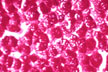

Glycogen storage PAS stain

Fig 31 - GLYCOGEN STORAGE: On H&E stain the cytoplasm of the hepatocyte is clear and the cell membrane thick. Also the nucleus may be clear.Both cytoplasm and nucleus will be intensely positive on PAS stain,epecially in alcohol fixed specimens. These changes occur in vaious forms of hereditary glycogenosis and in acquired conditions such as diabetes,primary or induced by steroids. In diabetes there will be a large number of vacuolated noclei in the periportal area.Nuclear vacuolization ,however,may be seen without diabetes indicating that this finding is not diagnostic.It is a meaningless frequent change in autopsy material.Glycogen nuclei are very numerous and periportal in Wilson's disease.Since nucear vacuolization occurs at an early presymptomatic stage of the disease, it cannot be overlooked in a liver biopsy because it may guide to an early diagnosis and a tempestive treatment. Glycogen loss is one of the first manifestations of hepatocellular injury.